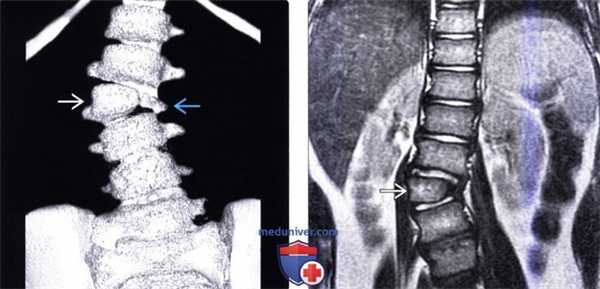

(Слева) Трехмерная КТ-реконструкция: несбалансированный правосторонний L3 полу позвонок, являющийся в данном случае причиной правосторонней сколиотической деформации. Корень дуги и задние элементы L3 позвонка слева в данном случае представлены рудиментарными фрагментами.

(Справа) На фронтальном Т2-ВИ грудопоясничного отдела позвоночника у пациента со сколиозом обнаружен сегментированный несбалансированный правосторонний L3 полупозвонок. Такая односторонняя несбалансированная конфигурация у данного пациента стала причиной врожденной сколиотической деформации.